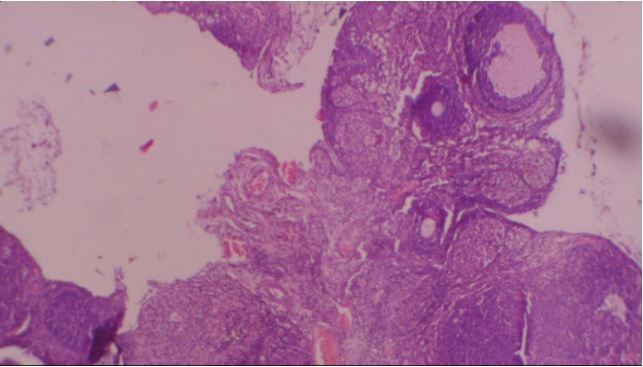

Figure 3: Photomicrograph of ovary of rat given 80 mg/kg VCD only showing: A. extruded follicles, B. active stroma congestion and C. stromal luteinization (H&E x40).

Figure 4: Photomicrograph of ovary of rat given 160 mg VCD only showing: A. active stromal congestion, B. stromal luteinization, C. degenerating follicles and D. tertiary follicle (H&E x40).